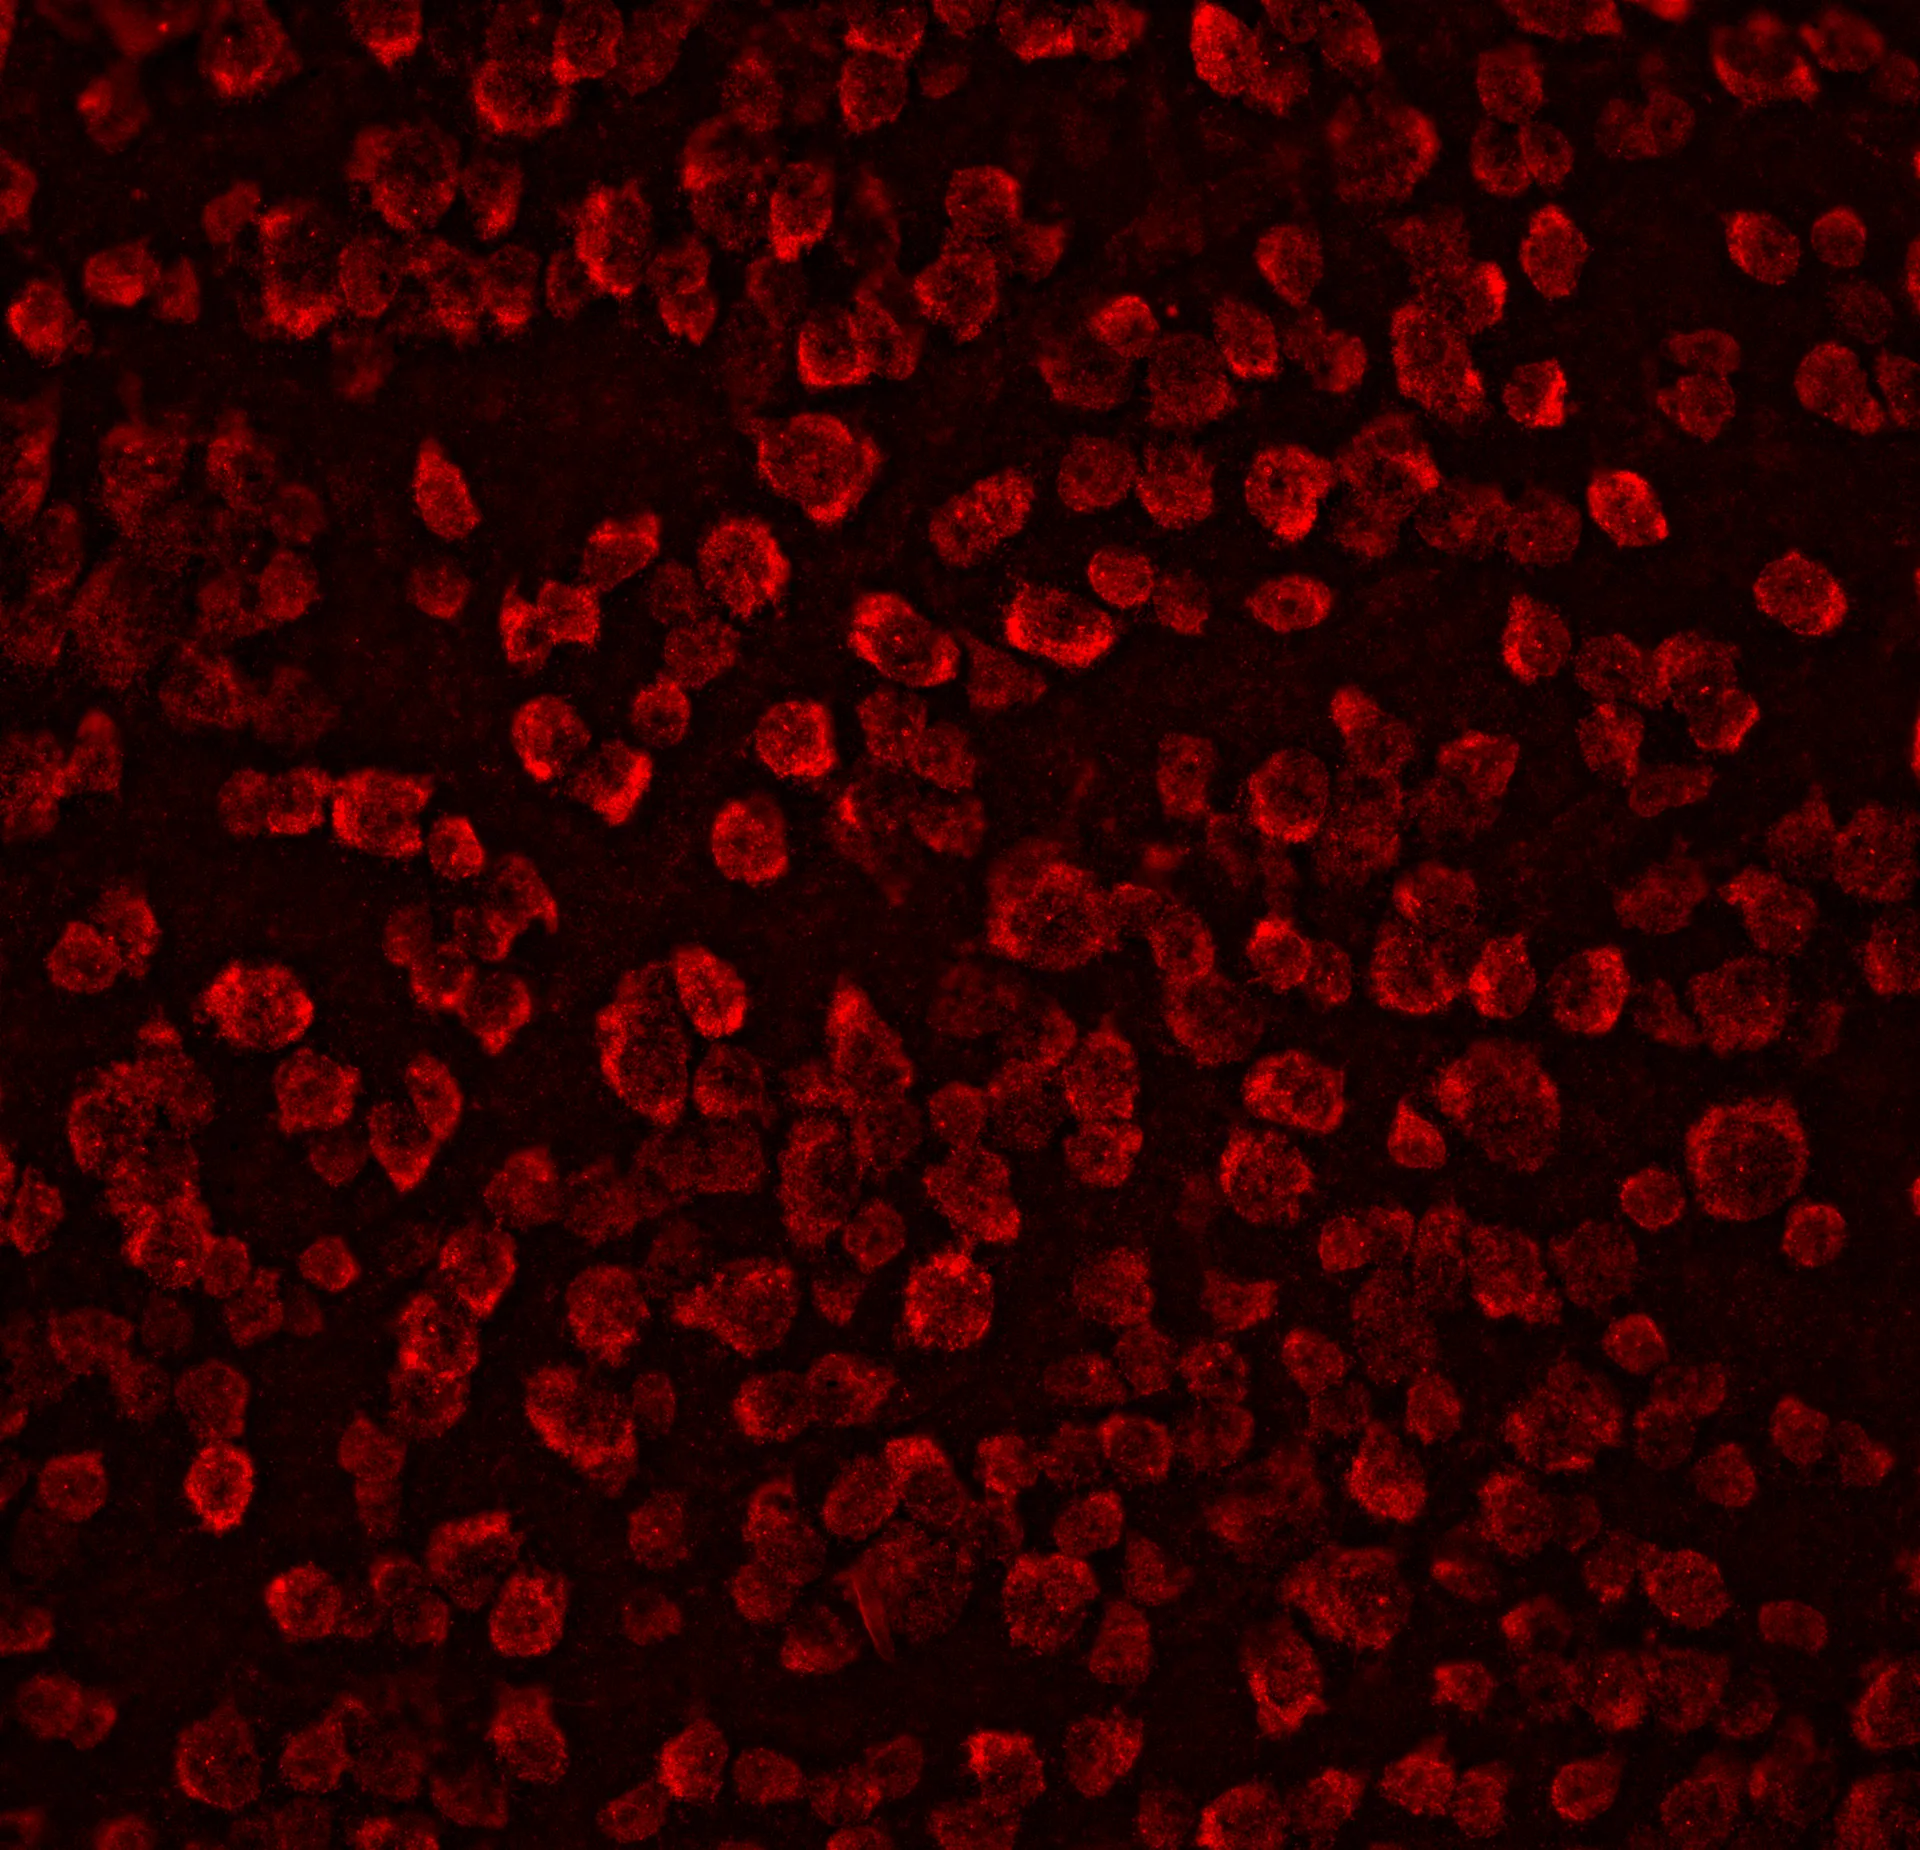

– Quantitative analysis of retinal ganglion cells loss

AI-driven analysis of retinal thickness measurements and retinal ganglion cell estimation using stereology ensures unbiased evaluations of neuroprotective treatments